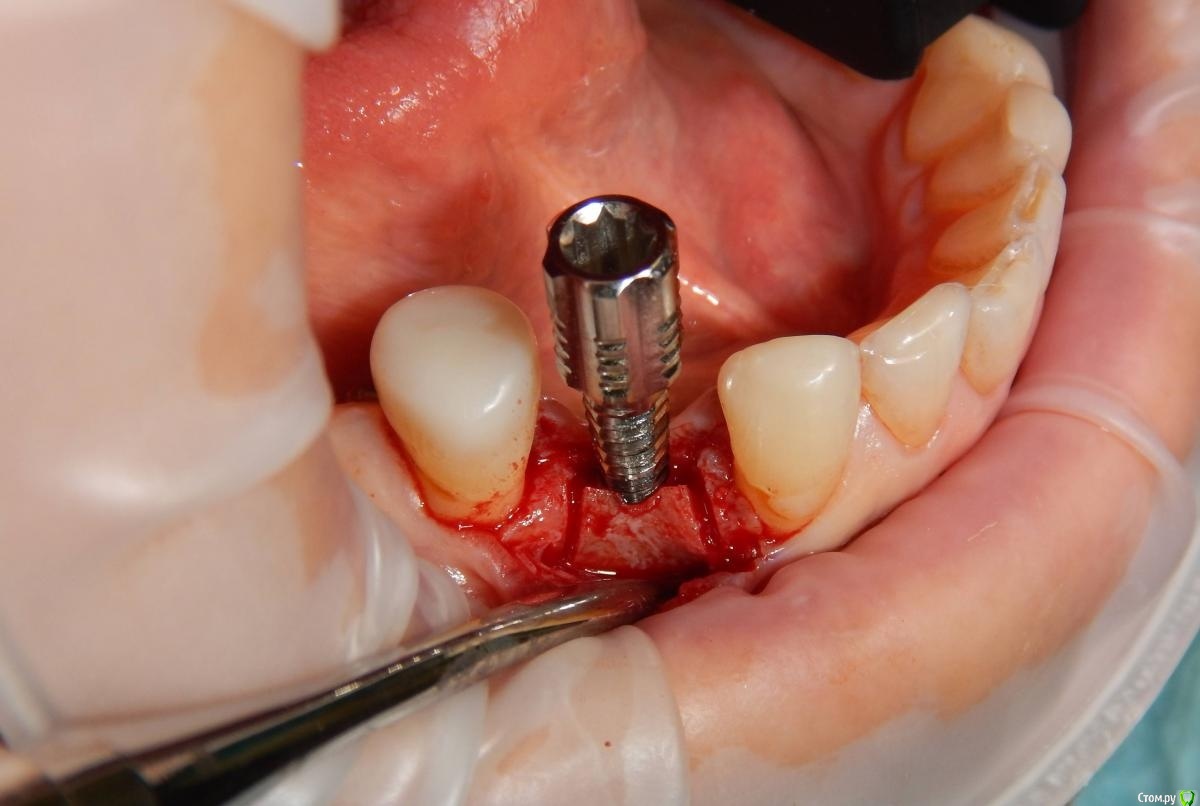

Astronaft Опубликовано 24 января, 2021 Поделиться Опубликовано 24 января, 2021 (изменено) Одиночный цирнокиевый имплантат и расщепление без графта. Пациентка:тонкая хрупкая женщина 55 лет, сконцентрированная на своем здоровье, в некоторой мере мнительная.всегда тяжелые заживления после удалений (по опросам)есть результаты Клиффорд теста (такая книжка под 200 страниц с in vitro аллерго-пробами на все известные материалы) Поставленная цель:только цирконий Мне было интересно найти вариант найболее приемленый пациентке и мне. С минимом хирургического риска и риском сожаления пациентки про выбор костного материала. Во-первых, я не использую аллографты - философски, чужие протеины, неприятный запах - просто основываясь на своем мнении.Во-вторых, мнительные пациенты склонны "пойти и почитать" до или потом и как следствие внушить себе вещи которых может и не было. Но по скольку мысль материальна... Все обсудил заранее.План: ридж сплит (расщепление), имплантат без графта, свободный СТ графт; если случается вестибулярная рецессия - пилим зирконий во рту. Ридж сплит сделан пьезотомом - крестальный и вертикальные пропилы на глубины около 8-10мм.Пилотное сверло.Развдвинул кость остеотомами от 1.6мм до 3.5мм в диаметре.Очень мягкая кость - напомнила мегкую максиллу плотности ногтевой пластинки вестибулярно.Имплант встал легко, но торк 40нсм. СТ графт из области 18. Деэпителизирую скальпелем уже потом. Тут интересно отметить, что я перестал боятся ошметков эпителия.Пончо сверху имплантата (а-ля шашлык Карлоса).Швы. PTFE всегда хорош. 12 недель.Красивая десна.Периотест -5.8 - отличный результат.Оттиск. Циркониевая коронка симметричная другой стороне. Изменено 24 января, 2021 пользователем Astronaft 19 Ссылка на комментарий

Astronaft Опубликовано 25 января, 2021 Автор Поделиться Опубликовано 25 января, 2021 Спасибо.День операции, 12 недель, день цементировки. 3 1 Ссылка на комментарий